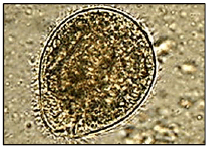

Um paciente foi diagnosticado com esquistossomose. Qual figura dentre as apresentadas abaixo pode ser a foto encontrada nas fezes desse paciente?